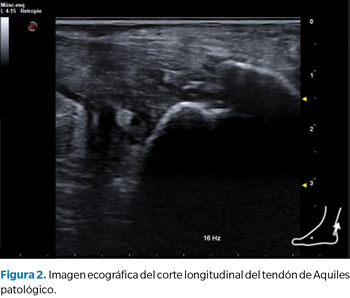

Esta aplicación de la ecografía como herramienta predictiva puede ser interesante desde el punto de vista de la investigación o incluso en la práctica clínica en determinados ámbitos como el deporte, con el objetivo de desarrollar planes de prevención si se encuentran alteraciones ecográficas significativas. Sin embargo, pensamos que en la práctica clínica “habitual” este uso de la ecografía no es tan aplicable ni útil como la ecografía que realizamos para la valoración morfofuncional o el uso como herramienta de feedback visual y guía de abordajes invasivos (Figura 2).

• Otros parámetros: fruto del análisis informático de la imagen ecográfica obtenemos otros parámetros que nos pueden aportar mayor información sobre la estructura del tendón de Aquiles, como la eco-intensidad, eco-varianza y ecogenicidad media36,37. Por ejemplo, en un estudio realizado en cadáveres38, se ha mostrado que la ecogenicidad media es un marcador que nos permite cuantificar el daño del tendón por fatiga. Este aspecto podría ser importante a la hora de valorar el riesgo lesional. Estos parámetros que dependen del análisis informático de la imagen ecográfica pueden tener más aplicación en la investigación que en la práctica clínica diaria (Figura 1).